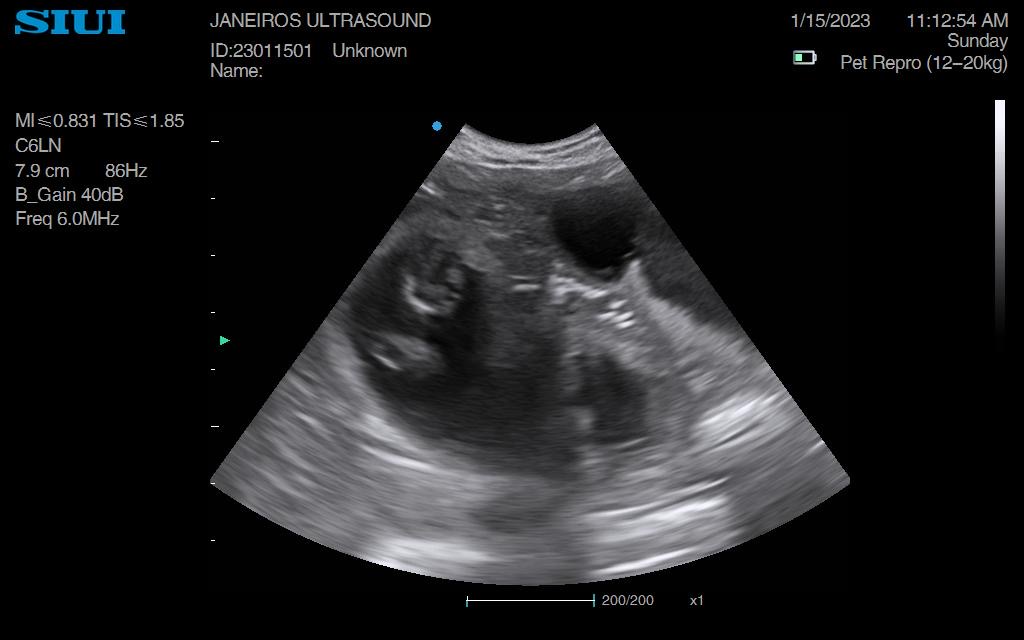

Spring forward to today. Measurements taken suggested 5wks and 1 day gestation and 6 sacs!!

Confirmed heartbeats on each puppy. All cooking away nicely.